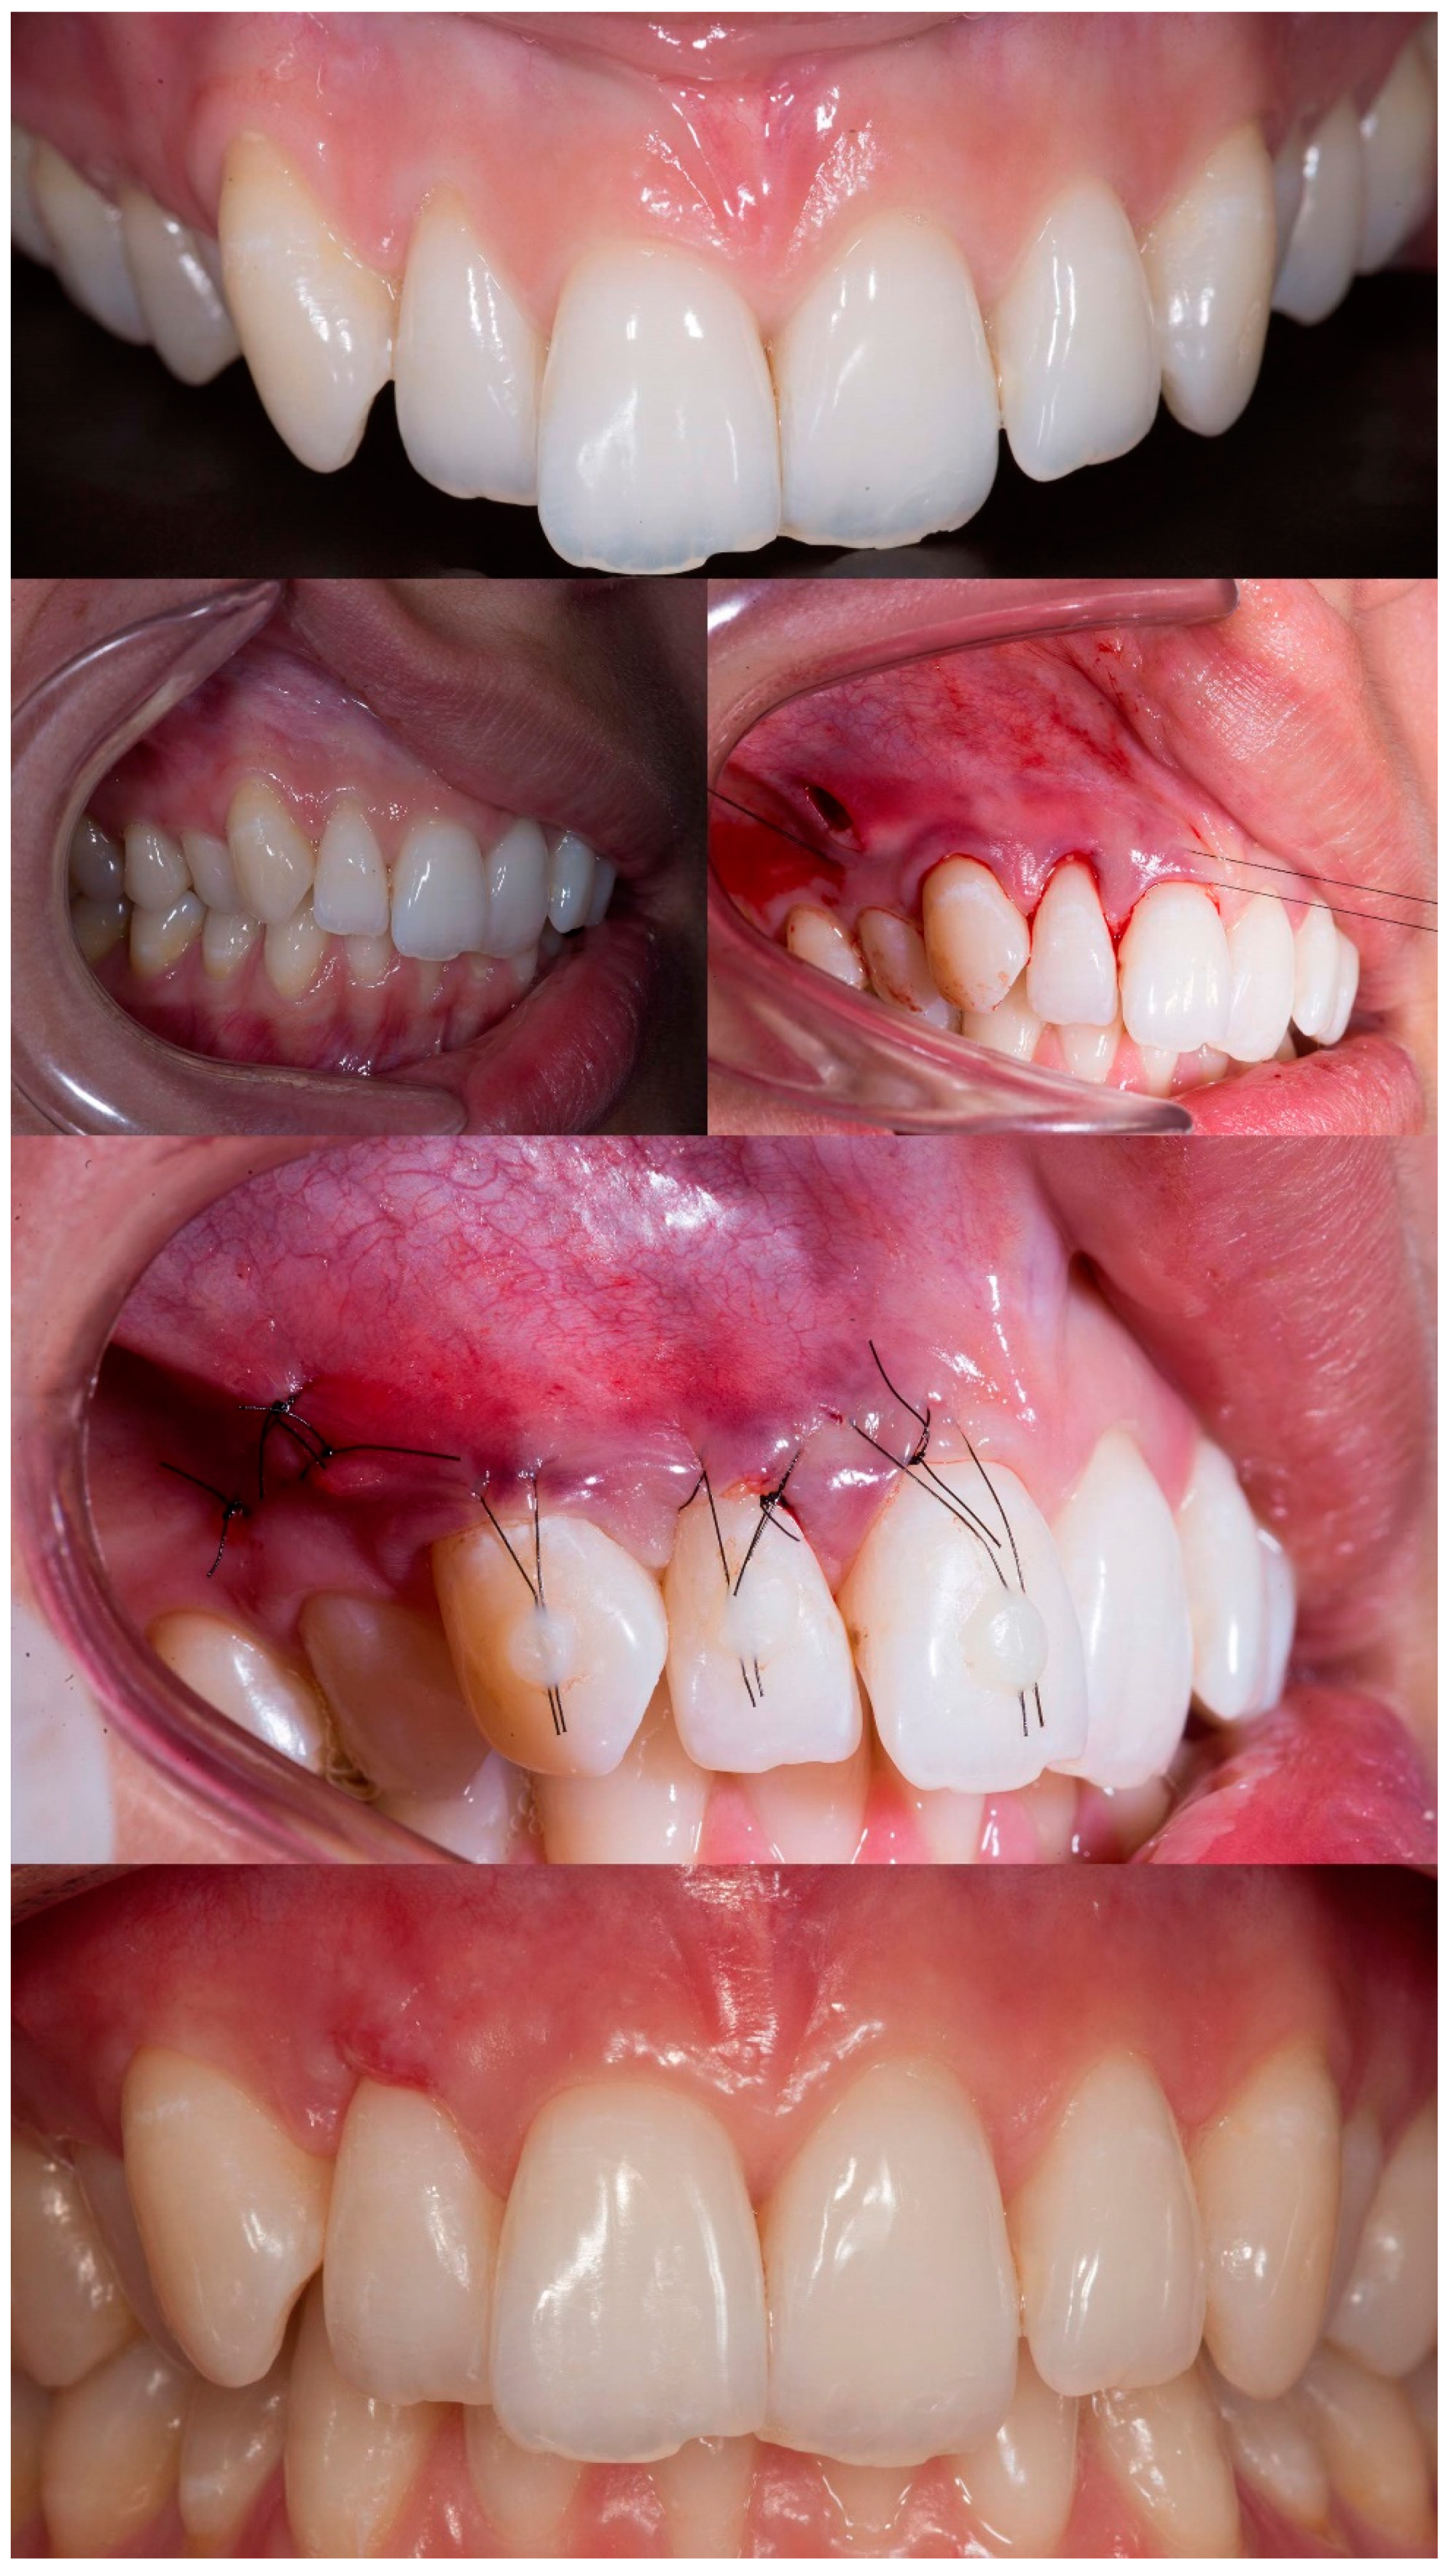

Figure 5.

Case 4 shows initial pictures of the GR defect (#41 and #31) and thin phenotype present; CTG over the receptor site with 2 distal vertical incisions to apply MiTT; suture performed; and the healing period after 6 months.

Case 4 presented GR in teeth #31 and #41, respectively, with 3mm and 1mm. The case was approached by applying two vertical incisions instead one in the distal of each involved tooth. The procedure and tissue manipulation happened without an event, and the result showed 100% RC (